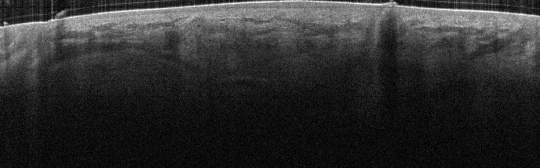

VA94: Right Forehead, Adjacent, Normal